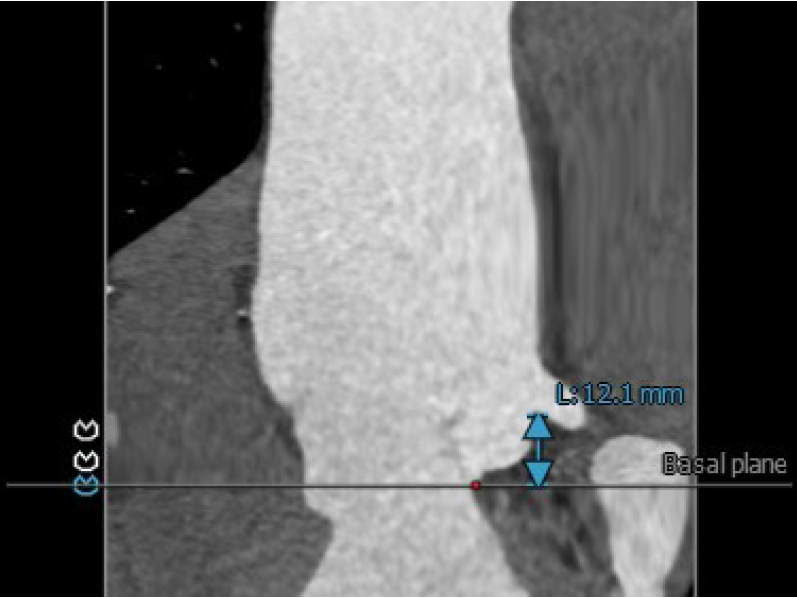

3.患者双侧冠脉开口高度可LCA:12.1mm,RCA:24.3mm。

左冠脉开口高度:12.1mm

右冠脉开口高度:24.3mm